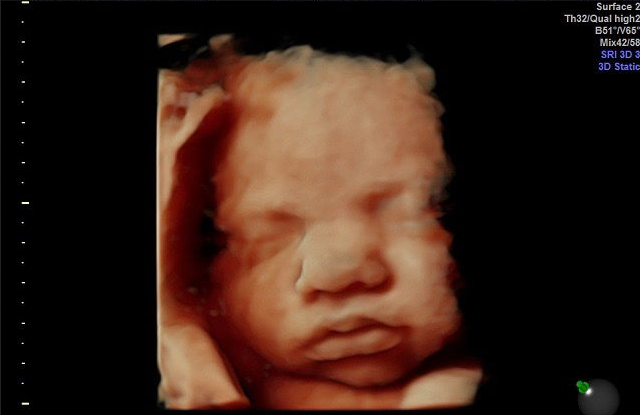

Court Affirms El Salvador’s Pro-Life Laws Saving Babies From Abortions

Most Premature Baby Ever Born in Ireland Heads Home to Spend Christmas With Family